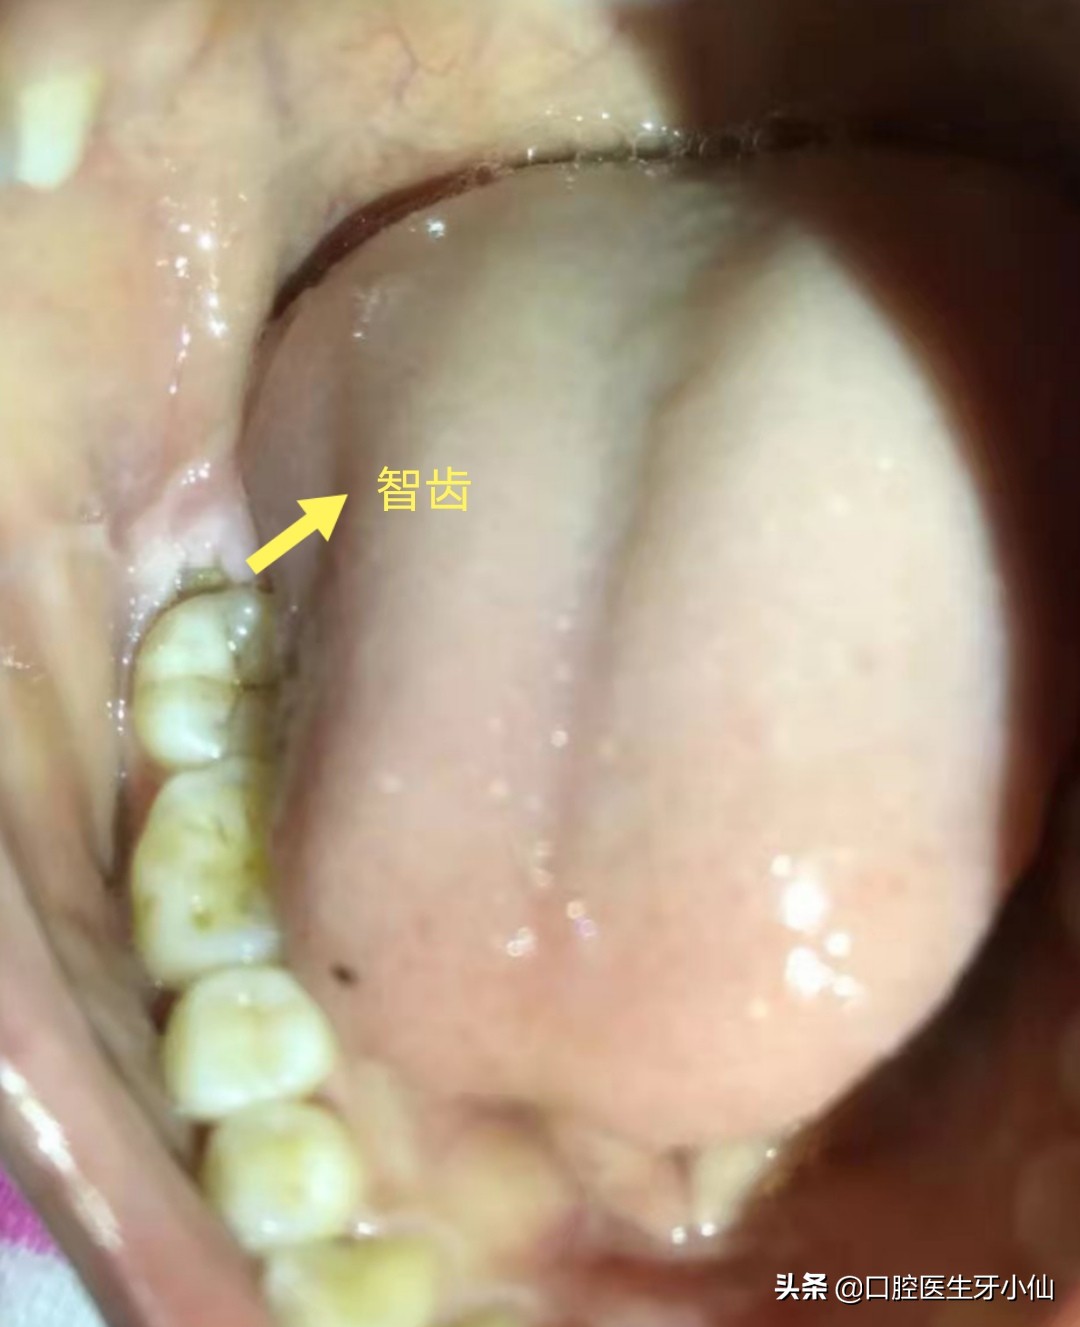

最后一颗牙疼?这很可能是智齿疼,智齿发炎了,口腔专业术语叫做“智齿冠周炎”。

由于智齿在口腔最后面,长的位置不好,智齿的后面还很可能有一块牙龈包裹,刷牙不容易刷干净,牙龈里面很容易堆积食物残渣,滋生牙菌斑,细菌进入到牙龈深处而导致牙龈发炎,导致牙龈发红、发热、肿痛,吞咽不适,严重的面部会有肿胀,甚至发热,这就是“智齿冠周炎”。